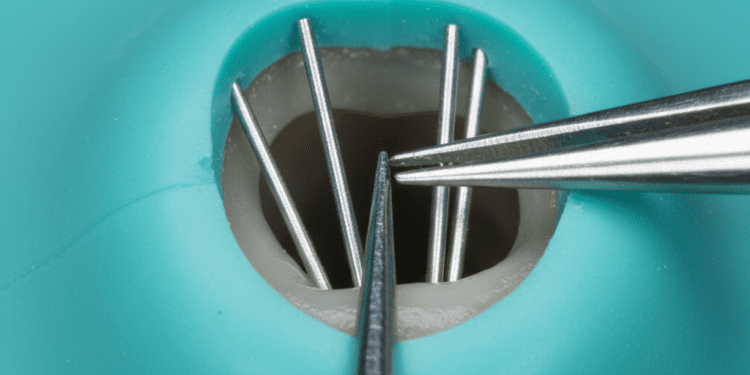

1. Detalhe Radiográfico

Um dos aspectos mais importantes é o nível de detalhe radiográfico da imagem. Altos níveis de detalhe permitem que professionals identifiquem pequenas fraturas, cáries incipientes e outras anomalias que poderiam passar despercebidas em imagens de menor qualidade. Para isso, é crucial que a tecnologia utilizada seja de ponta e que a técnica de exposição seja ajustada corretamente.